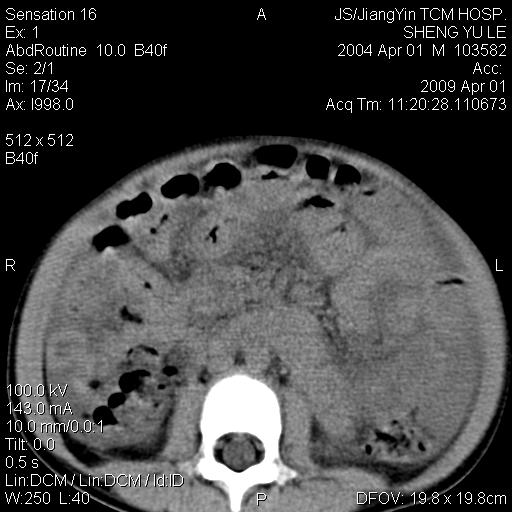

m,5岁。尿痛尿频数天。既往无病史。ct平扫腹盆腔积液。膀胱壁明显增厚。另可见心包增厚。wbc5万,骨髓穿等结果。请指教。

膀胱影像表现结合临床应该是急性膀胱炎症,但为什么有腹水呢?双肾输尿管无扩张,泌尿系压力应该不大不至于引起尿外渗,应该是腹膜感染引起的,但楼主没有提及相关症状,腹膜及膀胱结核?患者白细胞5万(结核不至于这么高啊),脾脏增大,是不是有白血病?进一步检查。。

不对,结核性腹膜炎也可以引起白细胞这么高,还是要看骨髓,另建议加抽腹水检查

腹水,膀胱壁增厚,wbc5万,结合临床,支持感染性疾病---感染性腹膜炎、腹水,急性膀胱炎,败血症。期待结果。